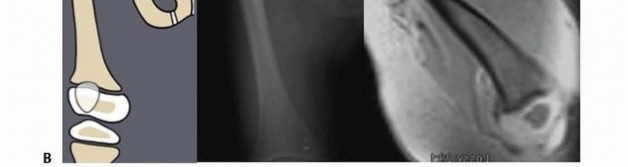

The resulting deformity is that seen with severe CFD ( FIG 2 ).

The proximal femur can also present a region of delayed ossification in either the subtrochanteric region or the neck region or both. Ossification of the cartilaginous proximal femur differentiates Paley type 1a CFD (ie, normal ossification) from Paley type 1b CFD (ie, delayed ossification). The latter can be subclassified as Paley type 1b

subtrochanteric type, neck type, or combined subtrochanteric-neck type (see FIG 1 ).

Once treated with realignment and in some cases insertion of bone morphogenetic protein (BMP), the unossified cartilage of the proximal femur in the type 1b will ossify changing the femur into type 1a. This area of delayed ossification is often mistaken for a pseudarthrosis (it could be referred to as a stiff cartilaginous pseudarthrosis to differentiate it from type 2, in which there is a true mobile, fibrous pseudarthrosis).

A more severe form of CFD is classified as Paley type 2; this type has a true mobile pseudarthrosis between the greater trochanter and femoral head or complete absence of the femoral head (see FIG 1 ).

Illustration 3 for Treatment for Congenital Femoral Deficiency: What You Need to Know Illustration 4 for Treatment for Congenital Femoral Deficiency: What You Need to Know Illustration 5 for Treatment for Congenital Femoral Deficiency: What You Need to Know Illustration 6 for Treatment for Congenital Femoral Deficiency: What You Need to Know FIG 2 • A. Paley type 1b CFD (subtrochanteric type) shown by illustration, radiograph, and MRI. Note the nonossified subtrochanteric cartilage B. Paley type 1b CFD (neck type) shown by illustration, radiograph, and MRI. Note the nonossified neck. *